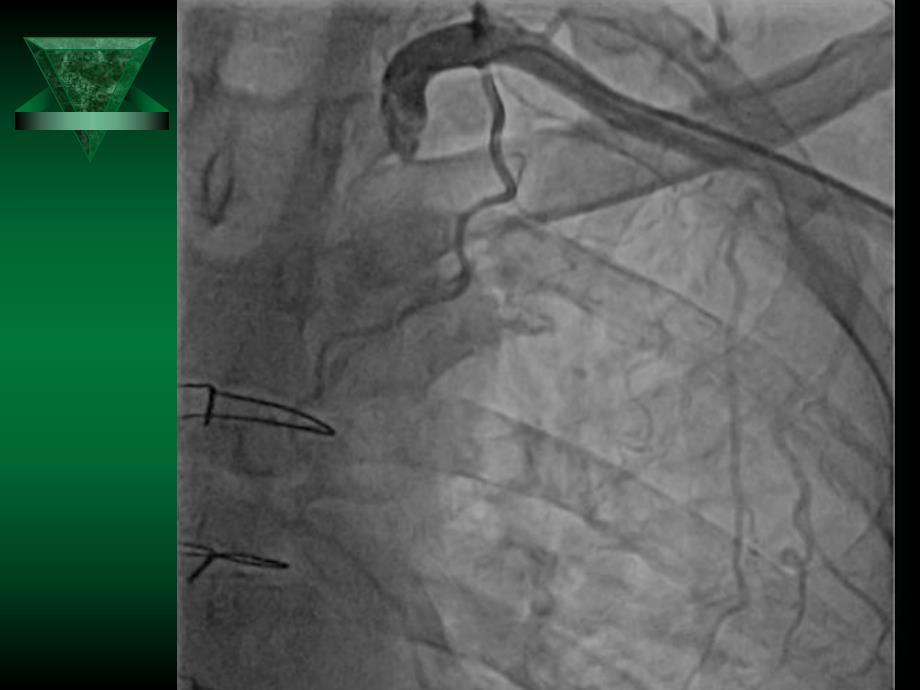

1、桡动脉穿刺点止血及桡动脉止血器应用桡动脉穿刺点止血及桡动脉止血器应用中国人桡动脉的平均直径男性:3.10.6 mm女性为2.80.6 mm完全可以通过6Fr(约折合2.1mm)造影导管或指引导管 加压时间加压时间4Fr、5Fr从加压开始1.5小时后,将压力减半(实际操作时将旋钮反向旋转13圈)。从弹力绷带放松一半后开始,1.5小时后,可视情况完全解压。6Fr 从加压开始2小时后,将压力减半(实际操作时将旋钮反向旋转13圈)。从压力减半开始计算,2-4小时后,可视情况完全解压。穿刺原因导致的止血穿刺原因导致的止血困难困难1,穿刺针多次刺入桡动脉,导致桡动脉多个破口出血。2,穿刺过程中残留血肿,压

2、迫困难。3,穿刺过程中穿入分支,止血器压迫很难垂直压迫,导致止血困难。4,穿刺后,切皮时进刀过深,导致动脉割伤,甚至割断桡动脉。5,操作过程中,泥鳅钢丝穿出前臂血管,导致前臂血肿及前臂静脉回流障碍。止血器使用不当导致止血失败止血器使用不当导致止血失败1,压迫部位过低,未能准确压迫实际的动脉穿刺点。2,患者过渡活动腕关节,扭转前臂导致止血器压迫点移位。3,松解止血器时,压迫点压力减低过快,导致动脉出血,需二次压迫。腕管综合症 1P:Pain2P:Pale3P:Pulseless1)疼痛:创伤后肢体持续剧烈疼痛,且进行性加剧,为本征最早期的症状。至晚期,感觉消失,可无疼痛。2)指或趾呈屈曲状态,肌力减弱。被动伸指或趾时可引起剧痛。3)患室表面皮肤略红,皮温稍高,有严重压痛,触诊可感到室内张力增高。4)远侧脉搏和毛细血管充盈时间正常。若不及时处理,将发展成缺血性肌挛缩。其主要表现为:由疼痛转为无痛;苍白或发绀、大理石花纹等;感觉异常;肌肉瘫痪;无脉。可能发生的并发症可能发生的并发症血肿出血桡动脉闭塞、末梢血管血流障碍局部感染皮肤过敏局部皮肤坏死一、加压扎紧止血带;调整旋钮压迫出血点;拔除鞘管二、左手适度加压,拔除鞘管;加压扎紧止血带;调整旋钮致穿刺点不出血1.52小时止血带减压时,只须反向旋转13圈,即可达到效果。1,安全可靠2,操作方便3,容易调整